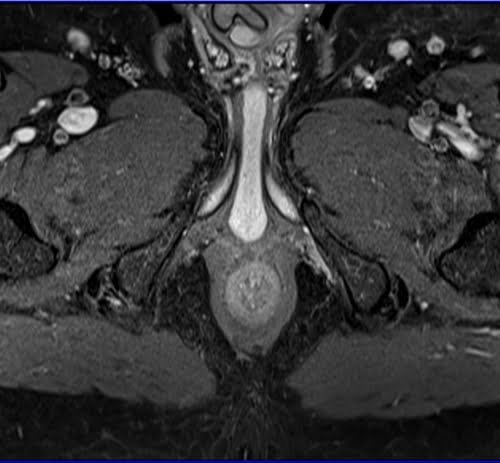

Prostatectomy patients prostate MRI T1 fat sat post contrast axial high resolution images